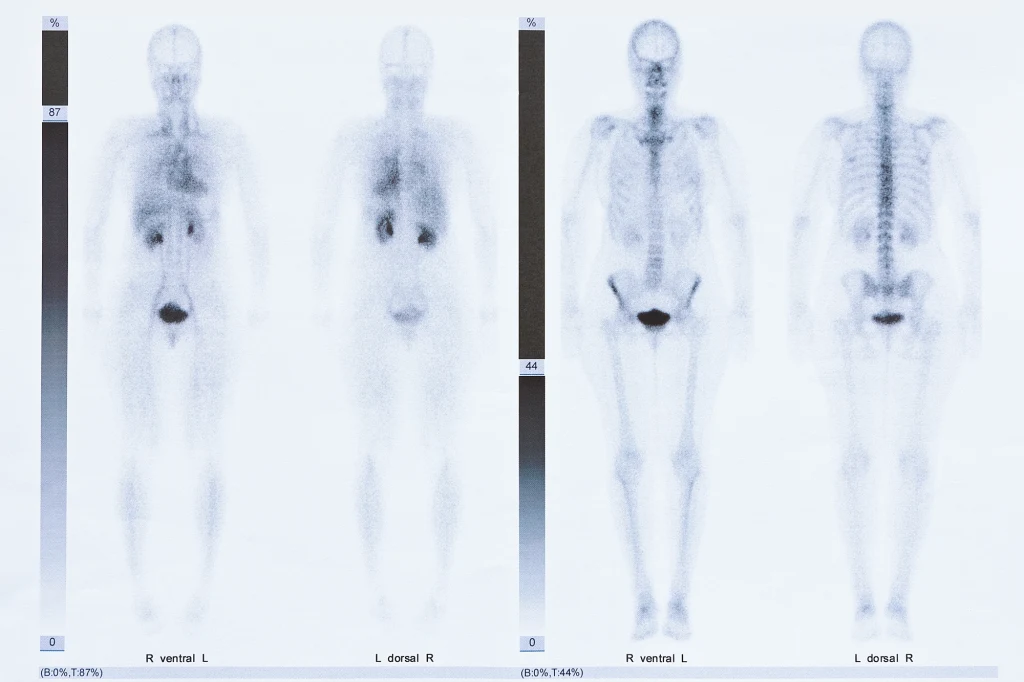

Pacjent najpierw otrzymuje niewielką dawkę izotopów promieniotwórczych (tzw. radioznaczników). Czasem scyntygrafię wykonuje się zaraz po podaniu radioznacznika, a czasem trzeba jednak poczekać (w przypadku tarczycy ok. 15 minut, wątroby – ok. 20 minut, kości – ok. 3 godziny), aby oceniany narząd zdążył go wchłonąć.

Następnie pacjent zostaje umieszczony przed tzw. gammakamerą. W jej głowicy znajduje się specjalny kryształ, który wychwytuje promieniowanie, jakie emituje badany narząd po pochłonięciu izotopu. Program zainstalowany w komputerze połączonym z gammakamerą przetwarza dane z głowicy na obraz organu widoczny także na monitorze. Scyntygrafię wykonuje się tylko na zlecenie lekarza. Jest bezpieczna, można się jej poddawać w każdym wieku (dotyczy to nawet noworodków) i powtarzać wielokrotnie. Przeciwwskazaniem jest tylko ciąża.